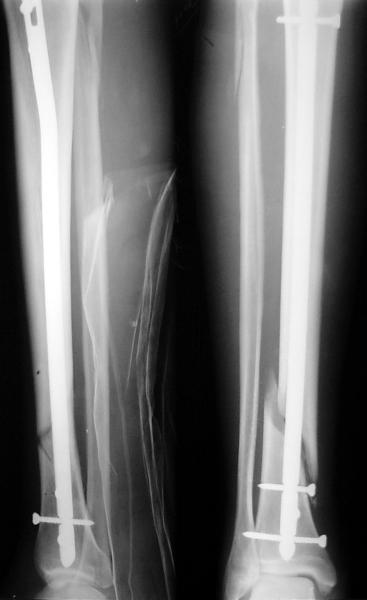

По крайней мере ходящих без дополнительной опоры через 1 месяц после операции с небольшой - при изолированной травме немало. Нестабильные по оси, кстати, не только оскольчатые, но и спиральные.

И если пациент еще не возвращается к полной нагрузке и функции, то не потому, что не разрешает врач, опасаясь несостоятельности фиксации.

Как мне показать пример? Фото стоящего на одной оперированной конечности пациента? O! Пример, подвигнувший нас на некоторое изменение технологий. Пациент этот ходил с полной нагрузкой вопреки рекомендациям. В качестве подтверждения - сломанный проксимальный статический винт к 1 мес., а к 2 мес. - все остальные. Сейчас мы перешли на более fool-proof остесинтез.

На мой взгляд, на снимках, приведённых Вами - неправильно сростающийся перелом дистальной трети большеберцовой кости, состояние после остеосинтеза интрамедуллярным гвоздём.

Как Вы пишите снимок под номером 1 - менсяц после операции, под номером 2- два месяца после операции.

Вы не послали послеоперационный снимок, поэтому трудно судить о состоянии редукции после операции.

Установка с медиальной стороны гвоздя в области дистального фрагмента дополнительного шурупа помогло бы Вам репонировать и удержать перелом в анатомическом положении, предотвратило варусную деформацию и смещение по ширине.

I think that the X-Rays show S/P IMN of Spiral # of the Distal Tibia consoles in misalignment.

You wrote that a picture number 1 - f month after the surgery, and number 2-two months after the surgery.

You have not sent a postoperative X-Rays; so it's impossible to discuss about the condition of a reduction after operation.

Let to express concerning technique of operation my opinion... Insertion of a screw to medial side of a nail in distal fragment would help you to reduction and to keep this fracture in anatomic position has prevented varus deformity and displacement on width. By the way, if it is possible send a postoperative picture.